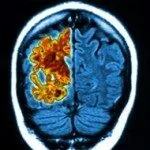

L’esposizione a limitate concentrazioni di rame è in grado di alterare la funzionalità della proteina LRP1, cruciale per lo smaltimento della proteina beta-amiloide che forma le placche caratteristiche della malattia di Alzheimer. Lo afferma un nuovo studio che presenta la prima prova sperimentale di un coinvolgimento del metallo nell\’insorgenza della patologia (…)

“È chiaro che, con il tempo, l’effetto cumulativo del rame è quello di danneggiare i sistemi cerebrali dai quali non può essere rimossa la proteina beta-amiloide”, ha spiegato Rashid Deane, ricercatore del Dipartimento di Neurochirurgia dello University of Rochester Medical Center (URMC) che ha coordinato lo studio. “Occorre però cautela nel valutare questi risultati perché il rame non è un elemento fondamentale per molti processi fisiologici e l’esposizione utilizzata nella ricerca è equivalente a quella consumata da molti cittadini con la normale dieta”.